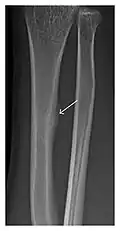

Figure 8: Proximal diaphyseal fatigue fracture of the tibia in a 20-year-old man with a history of regular jogging. (a) Lateral radiograph shows no obvious fracture lines but a subtle localized medial tibial cortex periosteal reaction (arrows). (b) Sagittal reformatted CT image acquired 1-month after the radiograph shows a linear hypoattenuation in the tibial cortex (arrowhead), as well as obvious periosteal thickening (arrows). (c) Sagittal T2-weighted fat-saturated image acquired the same day shows an area of hyperintensity spreading over the proximal tibia (arrows), which is consistent with the presence of proximal tibial fracture.[1]